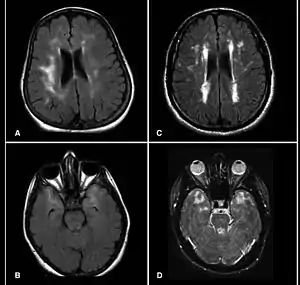

CADASIL is an inherited disorder caused by mutations in the Notch 3 gene located on chromosome 19.[19] The Notch 3 gene codes for a transmembrane protein whose function is not well-known. However, the mutation causes accumulation of this protein within small to medium-sized blood vessels.[19] This disease often presents in early adulthood with migraines, stroke, mood disturbances, and cognitive deterioration. MRI shows white matter changes in the brain and also signs of repeated strokes. The diagnosis can be confirmed by gene testing.[20]